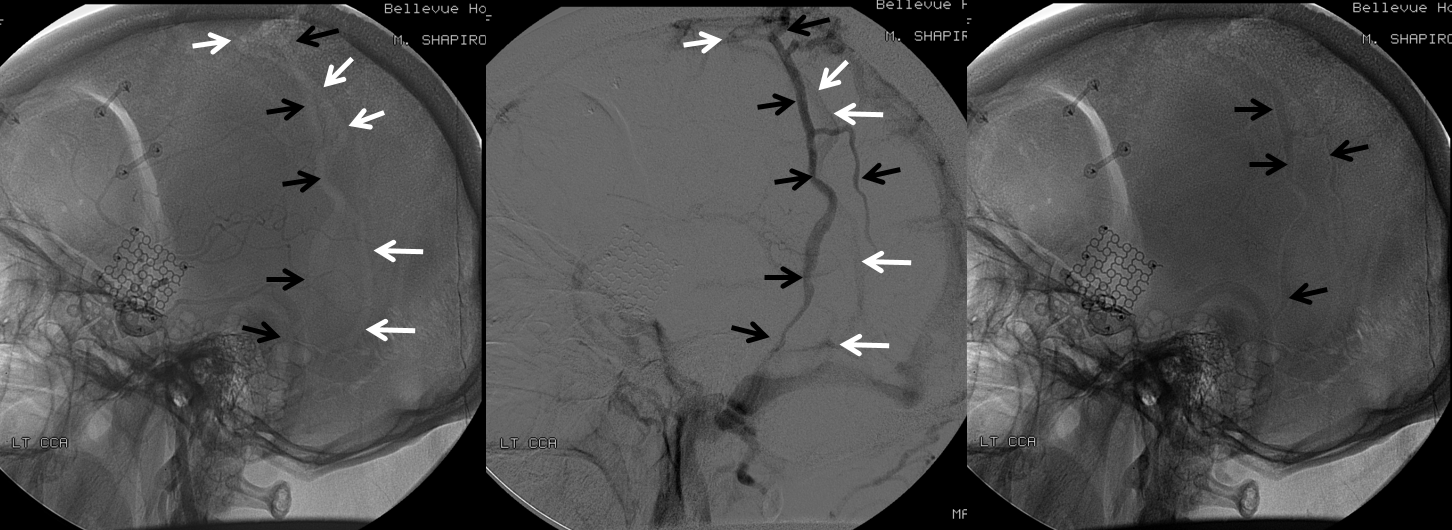

All of the above anatomic knowledge can become very useful in evaluation of venous thrombosis. Numerous collateral pathways develop in this setting attempting to compensate for the loss. The most dramatic cases usually involve the largest channel — the superior sagittal sinus. In this case, a man presented with what initially was thought to be vasculitis-related brain hemorrhage. Subsequent workup led to an angiogram, where sagittal sinus thrombosis with extensive trans-cerebral and trans-osseous emissary vein collateral channels was seen. In retrospect, these findings were present on the patient’s earlier contrast MRI. “Venovibe” or other contrast-enhanced MR venograms can very sensitive, particularly when interpreted with the appropriate index of suspicion. Noncontrast 2-D time of flight MRV I consider to be next to useless as a problem-solving technique. Any thin-slice postcontrast T1 study is vastly superior.